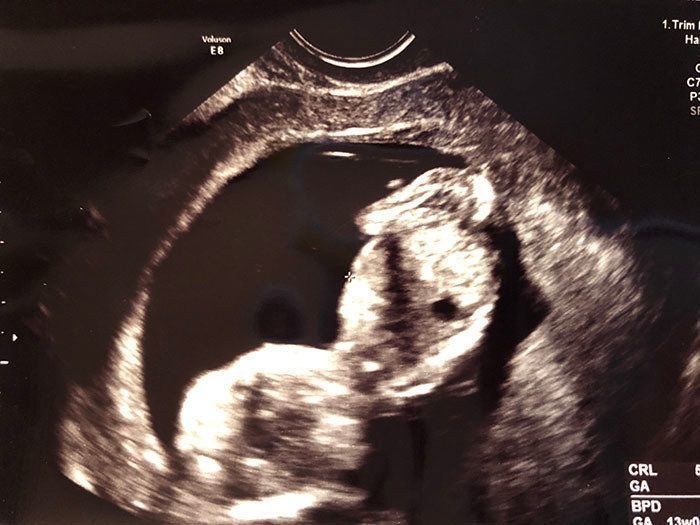

妊娠9週目 丸い胎嚢が、あっと言う間に人のカタチに!

前回のエコーには、丸い袋しか映っていなかった記憶があるのですが、妊娠9週目のエコーでは、もうすでに赤ちゃんの姿になって映っていました! 手足をばたつかせて泳ぐ姿がかわいくて感極まり、思わず涙が…。そして私はこの日、「私が守ってあげなくちゃ!」と、強く思ったのでした。